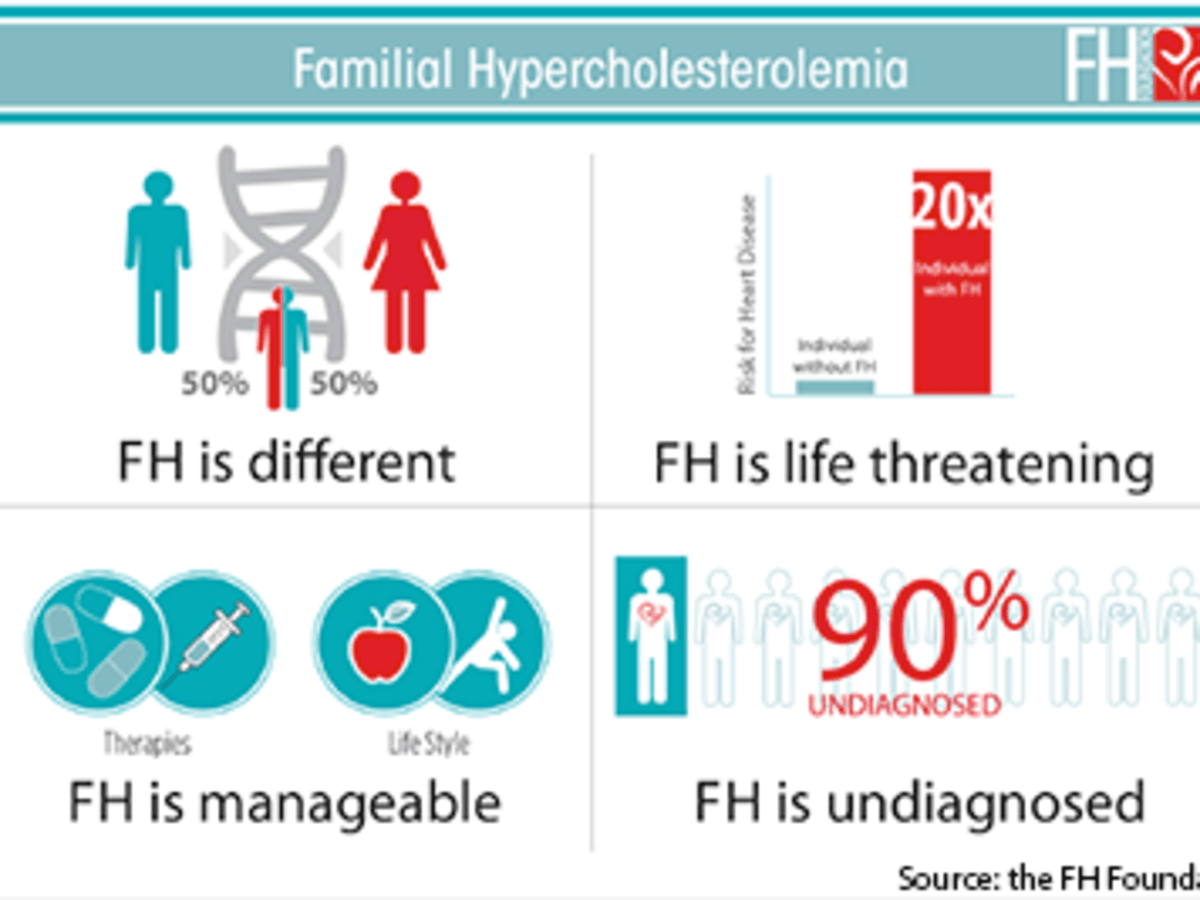

Novel Radiotracer Produces High Quality Images of “Alzheimer's Disease of the Heart” | Imaging Technology News, Unmasking the Genetics of Early Heart Disease - A Womans Health

Unmasking the Genetics of Early Heart Disease - A Womans Health